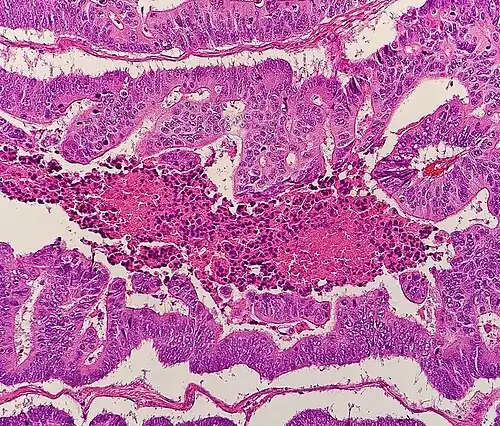

Histopathology

The histopathologic characteristics of the tumor are reported from the analysis of tissue taken from a biopsy or surgery. A pathology report contains a description of the microscopical characteristics of the tumor tissue, including both tumor cells and how the tumor invades into healthy tissues and finally if the tumor appears to be completely removed. The most common form of colon cancer is adenocarcinoma, constituting between 95%[99] and 98%[100] of all cases of colorectal cancer. Other, rarer types include lymphoma, adenosquamous, and squamous cell carcinoma. Some subtypes are more aggressive.[101] Immunohistochemistry may be used in uncertain cases.[102]